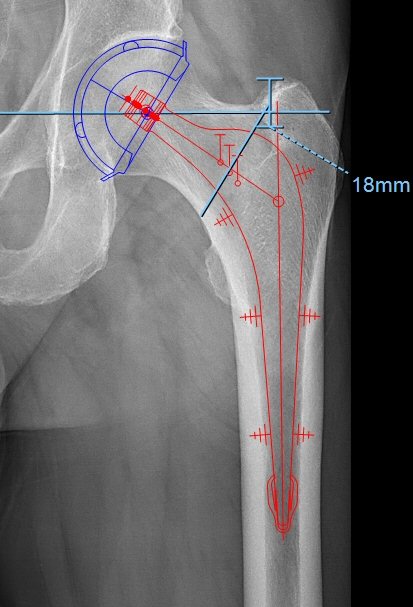

- Man kan mäta från stammens skuldra till toppen av trokanter major. Under operationen kan man sedan mäta i såret för att se att stammen hamnat rätt, stammens skuldra ca 18 mm distalt om spetsen på trokanter major i exemplet nedan.

Kupp, stam, offsetmätning, osteotomilinje och mätning av stammens placering i djupled